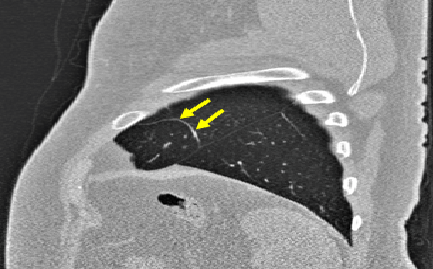

(1) Brain MR (2) Liver MR (3) Liver CT (4) Lung CT

We first introduce a method for connecting the output of a CNN to an ACM, yielding a model for the precise delineation of lesions, to which we refer as Deep Active Lesion Segmentation (DALS) (Figure 4). We then go further to introduce a truly unified framework (Figure 5) that bridges the gap between ACMs and CNNs by leveraging a novel, automatically differentiable level-set ACM with trainable parameters that allows for back-propagation of gradients and can be end-to-end trained along with a backbone CNN from scratch, without any CNN pre-training. The ACM is initialized directly by the CNN and utilizes an energy functional that is locally-tunable by the backbone CNN, through 2D feature maps. Thus, our work overcomes the big hurdle of fully automating the powerful ACM approach to image segmentation. We have applied our proposed framework to the task of building segmentation in aerial images (Figure 6).

Deep Active Lesion Segmentation

[45]: Lesion segmentation is an important problem in computer-assisted diagnosis that remains challenging due to the prevalence of low contrast, irregular boundaries that are unamenable to shape priors. We introduce Deep Active Lesion Segmentation (DALS), a fully automated segmentation framework that leverages the powerful nonlinear feature extraction abilities of FCNs and the precise boundary delineation abilities of ACMs. Our DALS framework benefits from an improved level-set ACM formulation with a per-pixel-parameterized energy functional and a novel multiscale encoder-decoder CNN that learns an initialization probability map along with parameter maps for the ACM. We evaluate our lesion segmentation model on a new Multiorgan Lesion Segmentation (MLS) dataset that contains images of various organs, including brain, liver, and lung, across different imaging modalities—MR and CT. Our results demonstrate favorable performance compared to competing methods, especially for small training datasets. -